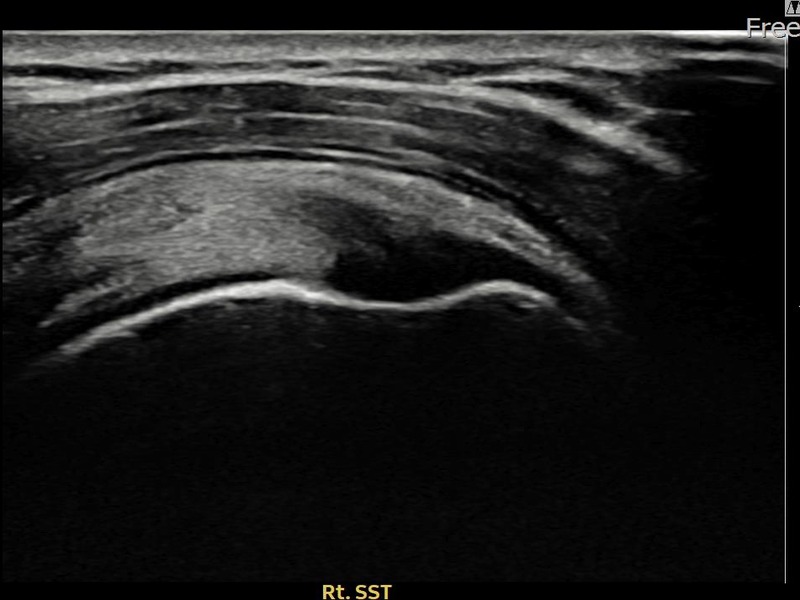

최ㅇㅇ님 · 우측 극상근건 관절면측 부분파열

우측 어깨 통증으로 수면과 일상 동작이 어려워 내원하셨습니다. 초음파 유도 하 축소봉합술 후 힘줄 연속성이 회복되었습니다.

상세 보기 →